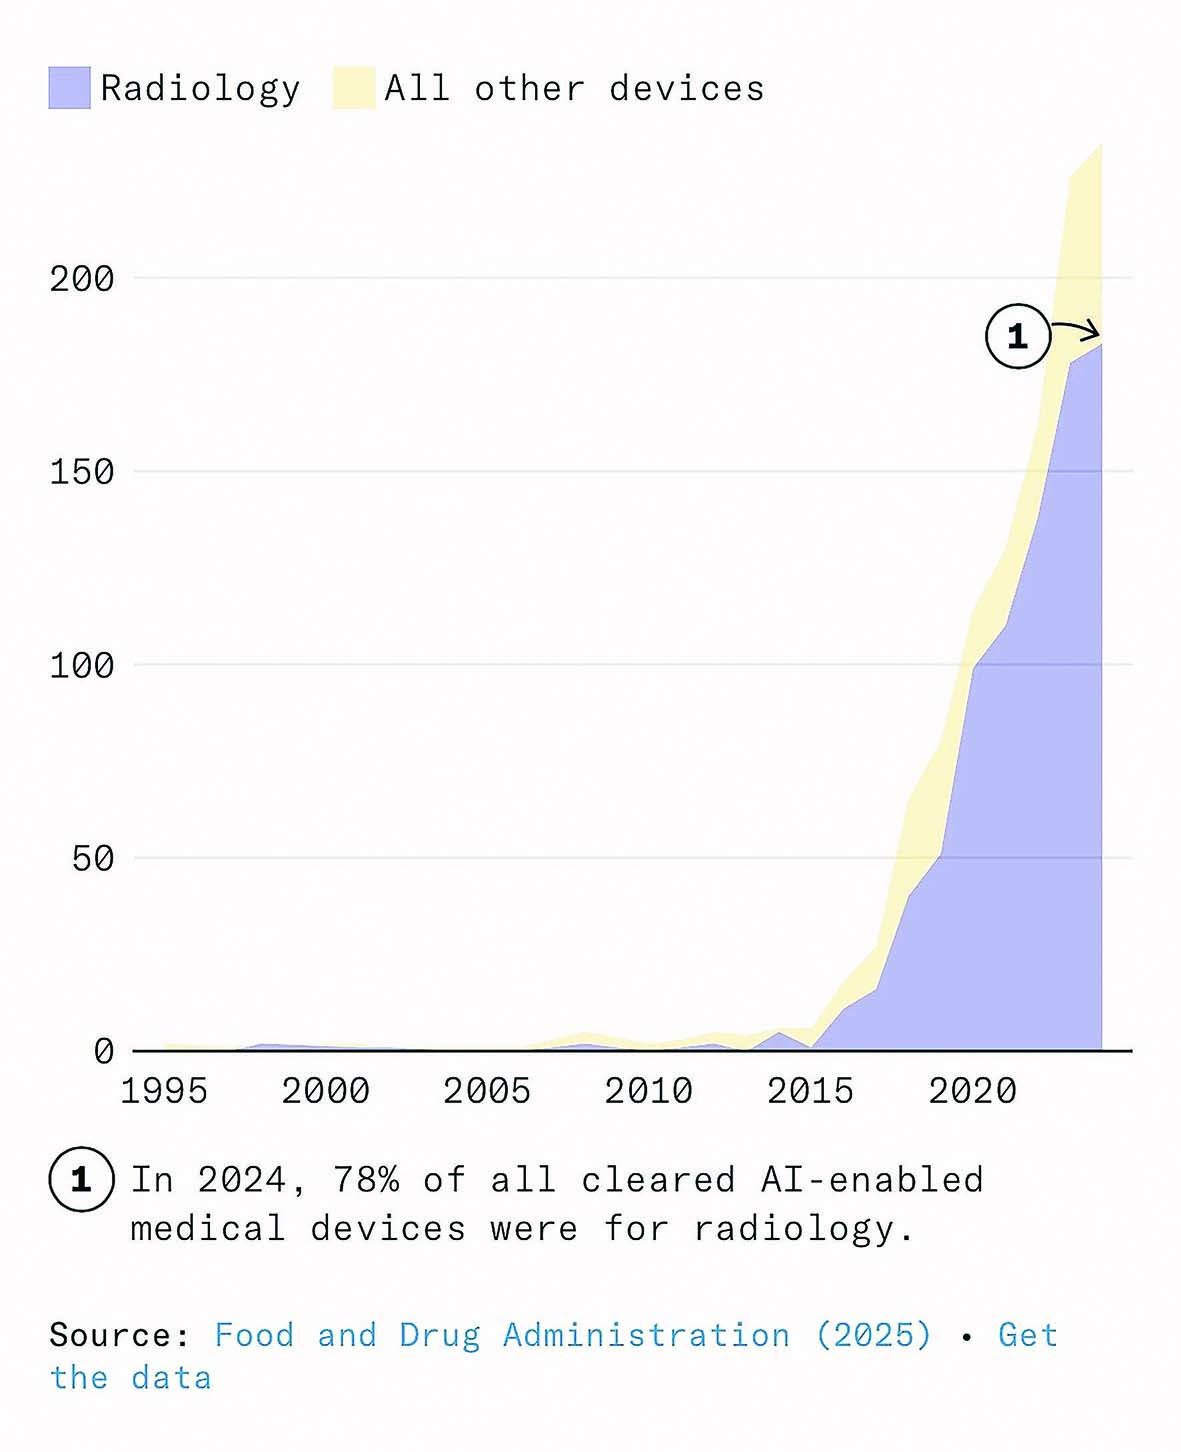

CheXNet میتواند ذاتالریه را با دقتی بیشتر از یک گروه رادیولوژیستهای دارای بورد تخصصی تشخیص دهد. این یک مدل هوش مصنوعی است که در سال ۲۰۱۷ منتشر شد و با بیش از ۱۰۰هزار تصویر اشعه ایکس قفسه سینه آموزش دیده است. این مدل سریع، رایگان و قابل اجرا روی یک کارت گرافیک معمولی خانگی است. یک بیمارستان میتواند از آن استفاده کند تا یک اسکن جدید را در کمتر از یکثانیه طبقهبندی کند. از آن زمان تاکنون شرکتهایی مانند Annalise.ai، Lunit، Aidoc، و Qure.ai مدلهایی ارائه کردهاند که میتوانند صدها بیماری را در انواع مختلف اسکن و با دقت و سرعتی بیش از رادیولوژیستهای انسانی در آزمونهای معیار، شناسایی کنند. برخی از محصولات میتوانند فهرست کاری رادیولوژیستها را دوباره مرتب کنند تا موارد بحرانی در اولویت قرار گیرند و مراحل بعدی را به تیم مراقبت پیشنهاد دهند، یا گزارشهای اولیه ساختاریافتهای تولید کنند که با سیستمهای ثبت بیمارستانی سازگار است. چند مورد مانند LumineticsCore، حتی مجوز دارند که بدون نیاز به بررسی عکس توسط پزشک کار کنند. در مجموع بیش از ۷۰۰مدل رادیولوژی دارای تاییدیه FDA وجود دارد که بیش از سهچهارم کل دستگاههای پزشکی مبتنی بر هوش مصنوعی را تشکیل میدهند.

رادیولوژی حوزهای است که برای جایگزینی نیروی انسانی بهینهسازی شده است؛ جایی که ورودیهای دیجیتال، وظایف مبتنی بر تشخیص الگو و شاخصهای روشن غالب هستند. در سال ۲۰۱۶، جفری هینتون، دانشمند رایانه و برنده جایزه تورینگ اعلام کرد که «از همین حالا باید آموزش رادیولوژیستها را متوقف کرد.» اگر افراطیترین پیشبینیها درباره اثر هوش مصنوعی بر اشتغال و دستمزدها درست بود، آنگاه رادیولوژی باید مانند قناری در معدن زغالسنگ عمل میکرد و اولین نشانههای خطر را نشان میداد اما تقاضا برای نیروی انسانی بیش از هر زمان دیگری است. در سال ۲۰۲۵، برنامههای رزیدنتی رادیولوژی تشخیصی آمریکا رکورد ۱۲۰۸ موقعیت رزیدنتی را در تمام تخصصهای رادیولوژی ارائه دادند؛ افزایشی ۴درصدی نسبت به سال ۲۰۲۴. نرخ خالی بودن جایگاهها در این حوزه نیز به بالاترین سطح تاریخ خود رسیده است. در سال ۲۰۲۵، رادیولوژی دومین تخصص پردرآمد پزشکی در ایالات متحده بود، با درآمد متوسط ۵۲۰هزار دلار، یعنی بیش از ۴۸درصد بالاتر از میانگین سال ۲۰۱۵.